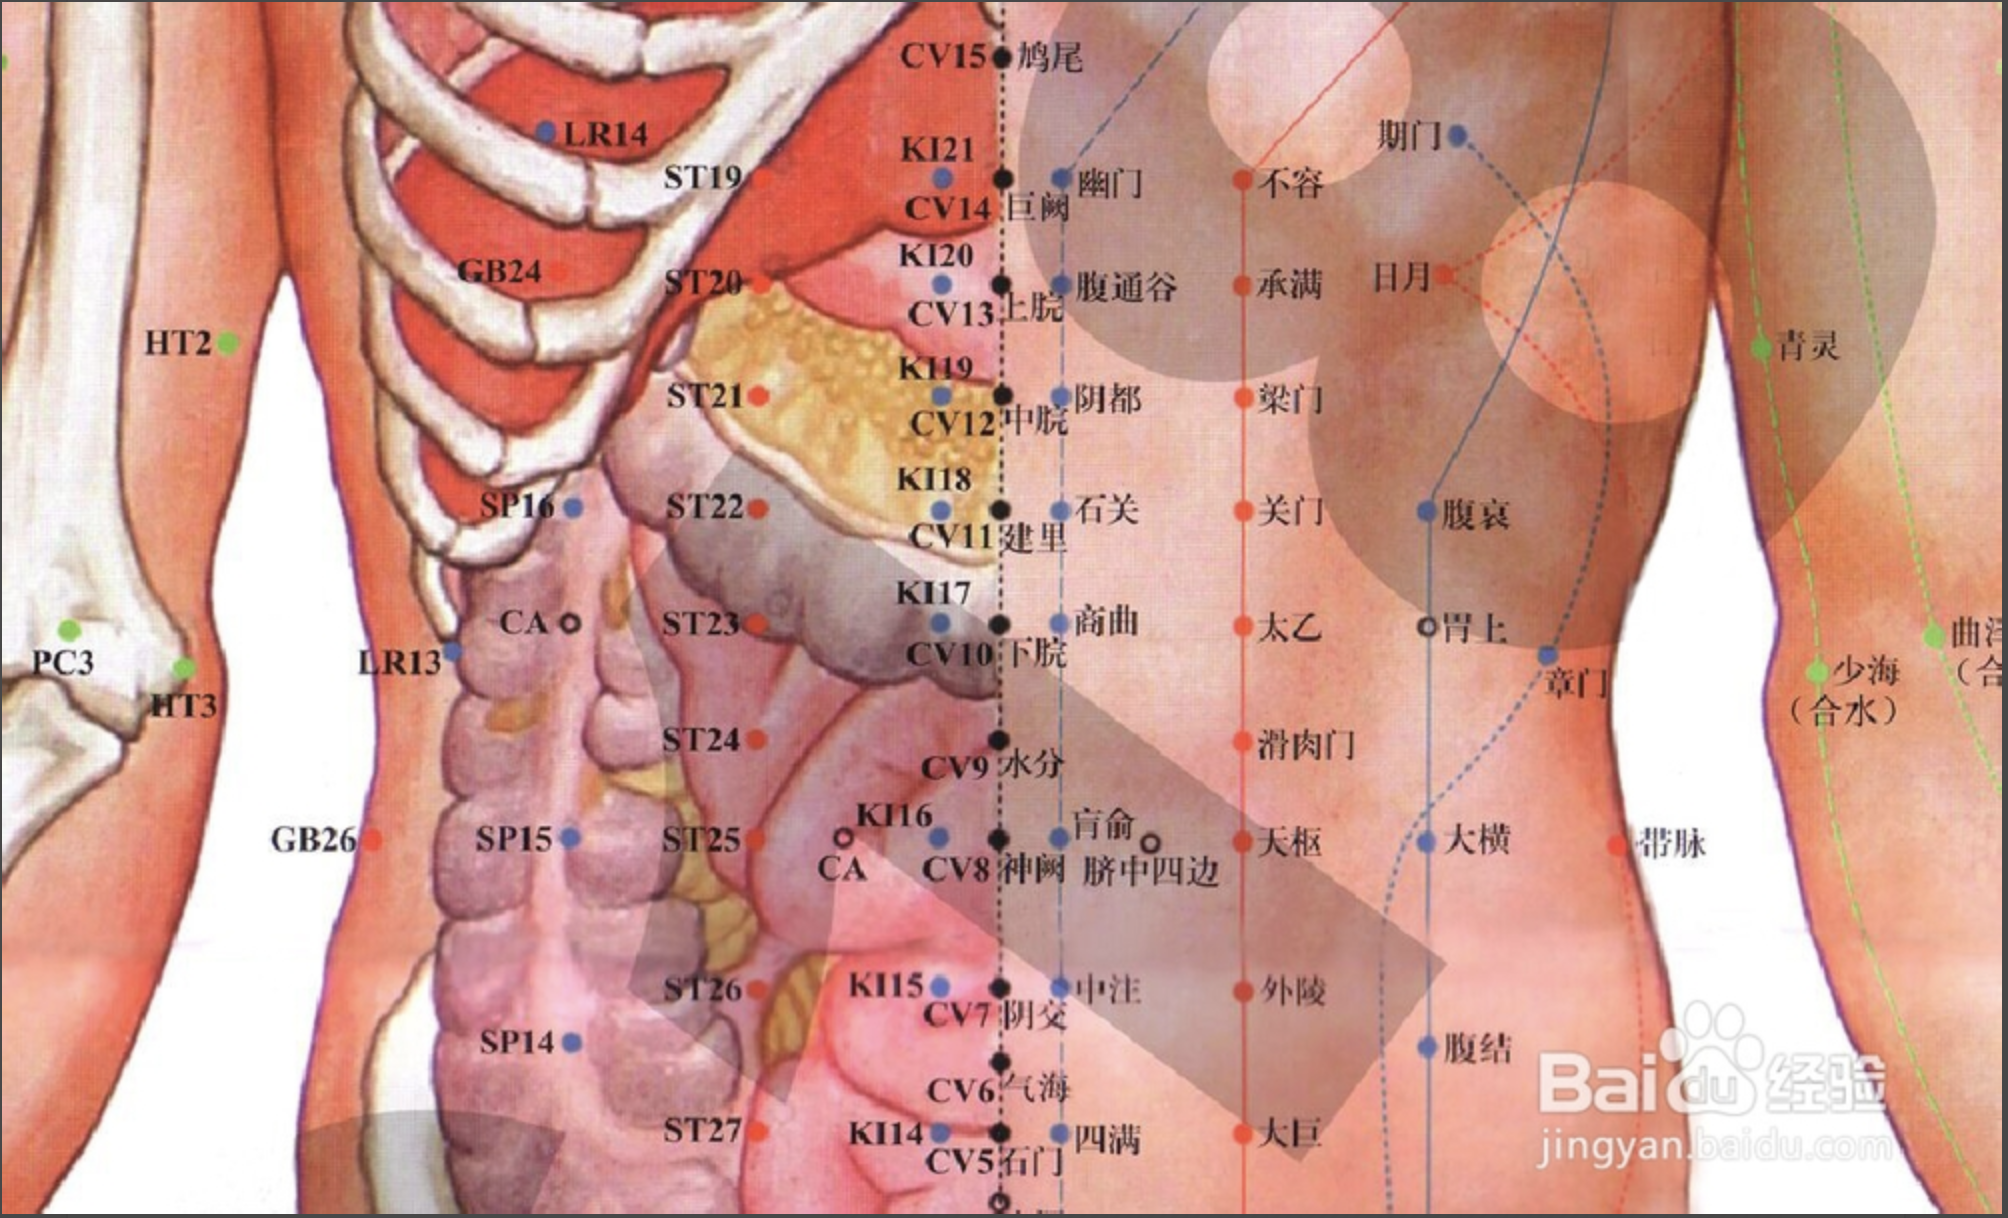

【(十四)任脉(图10-32-1)】

1、经脉循行 起于小腹内,下出会阴部,向上行于阴毛部,沿腹内向上经前正中线到达咽喉部,再向上环绕口唇,经面部入目眶下。

2、主要病候 疝气疝气、带下、腹中结块等。

3、主治概要 主治腹、胸、颈、头面的局部病证及相应的内脏器官疾病。少数腧穴有强壮作用或可治神志病。

4、督脉歌诀 任脉会阴两阴间,曲骨毛际陷中安,中极脐下四寸取,关元脐下三寸连,脐下二寸石门是,脐下寸半气海全,脐下一寸阴交穴,脐之中央即神阙,脐上一寸为水分,脐上二寸下脘列,脐上三寸名建里,脐上四寸中脘接,脐上五寸上脘在,脐上六寸巨阙穴,鸠尾蔽骨下五分,中庭膻下寸六取,膻中却在两乳间,膻上寸六玉堂主,膻上紫宫三寸二,膻上四八华盖举,膻上璇玑六寸四,玑上一寸天突取,廉泉颔下结上已,承浆颐前下唇中。

会阴

【定位】 在会阴部,男性当阴囊根部与肛门连线的中点,女性当大阴唇后联合与肛门连线的中点。

【主治】 溺水窒息,昏迷,癫狂,惊痫,小便难,遗尿,阴痛,阴痒,阴部汗湿,脱肛,阴挺,疝气,痔疾,遗精,月经不调。

【配伍】 配神门治癫狂痫,配水沟治溺水窒息,配十宣急救昏迷,配蠡(lí)沟治阴痒、阴痛(湿热下注型),配归来、百会治阴挺(中气下陷型),配承山治痔疮、脱肛,配支沟、上巨虚治便秘,配中极治遗尿、淋证,配关元治遗精。

【刺灸法】 直刺 0.5 ~ 1 寸,孕妇慎用;可灸。

中极

【定位】 在下腹部,前正中线上,当脐中下 4 寸。

【主治】 小便不利,遗尿不禁,阳痿,早泄,遗精,白浊,疝气偏坠,积聚疼痛,月经不调,阴痛,阴痒,痛经,带下,崩漏,阴挺,产后恶露不止,胞衣不下,水肿。

【配伍】 配大赫、肾俞、三阴交,次髎治阳痿、早泄、遗精、白浊、月经不调、痛经崩漏、产后恶露不止,胞衣不下、阴挺等证(肾气虚型),配阴谷、气海、肾俞治遗溺不止,配大敦、关元、三阴交治疝气偏坠,配水分、三焦俞、三阴交、气海、委阳治水肿,中极透曲骨配三阴交、地机治产后、术后尿潴留;中极透曲骨、配气海、膻中、足三里治尿潴留(老年人气虚)。

【刺灸法】 直刺 0.5 ~ 1 寸;可灸。孕妇慎用。

【附注】 足三阴、任脉之会。

关元

【定位】 在下腹部,前正中线上,当脐中下 3 寸。

【主治】 中风脱证,虚劳冷惫,羸瘦无力,少腹疼痛,霍乱吐泻,痢疾,脱肛,疝气,便血,溺血,小便不利,尿频,尿闭,遗精,白浊,阳痿,早泄,月经不调,经闭,经痛,赤白带下,阴挺,崩漏,阴门瘙痒,恶露不止,胞衣不下,消渴,眩晕。

【配伍】 配气海、肾俞(重灸)、神阙(隔盐灸)急救中风脱证,配足三里、脾俞、公孙、大肠俞治虚劳、里急、腹痛;配三阴交、血海、中极、阴交治月经不调(冲任不固,针用补法),配中极、大赫、肾俞、次髎、命门、三阴交治男子不育症、阳痿、遗精、早泄、尿频、尿闭、遗尿(肾阳虚衰、针补法或艾灸),配太溪、肾俞治泻痢不止、五更泄。

【刺灸法】 直刺 0.5 ~ 1 寸;可灸。孕妇慎用。

【附注】 足三阴、任脉之会。

气海

【定位】 在下腹部,前正中线上,当脐(qí)中下 1.5 寸。

【主治】 绕脐腹痛,水肿鼓胀,脘腹胀满,水谷不化,大便不通,泻痢不禁,癃淋,遗尿,遗精,阳痿,疝气,月经不调,痛经,经闭,崩漏,带下,阴挺,产后恶露不止,胞衣不下,脏气虚惫,形体羸瘦,四肢乏力。

【配伍】 配三阴交治白浊、遗精,配关元治产后恶露不止;配灸关元、膏肓、足三里治喘息短气(关元虚惫),配关元、命门(重灸)、神阙(隔盐灸)急救中风脱证,配足三里、脾俞、胃俞、天枢、上巨虚治胃腹胀痛、呃逆、呕吐、水谷不化、大便不通、泻痢不止(脾气虚弱),配足三里、合谷、百会治胃下垂、子宫下垂、脱肛。

【刺灸法】 直刺 0.5 ~ 1 寸;可灸。孕妇慎用。

【附注】 肓(huāng)之原穴。

神阙

【定位】 在腹中部,脐中央。

【主治】 中风虚脱,四肢厥冷,尸厥,风痫,形惫体乏,绕脐腹痛,水肿鼓胀,脱肛,泻痢,便秘,小便不禁,五淋,妇女不孕。

【配伍】 配三阴交治五淋,配公孙、水分、天枢、足三里治泻痢便秘、绕脐腹痛(脾肾不和),配长强、气海、关元治脱肛、小便不禁、肾虚、不孕症,神阙(隔盐灸)配关元、气海(重灸)治中风脱证。

【刺灸法】 禁刺;可灸。

中脘

【定位】 在上腹部,前正中线上,当脐中上 4 寸。

【主治】 胃脘痛,腹胀,呕吐,呃逆,反胃,吞酸,纳呆,食不化,疳积,鼓胀,黄疸,肠鸣,泄利,便秘,便血,胁下坚痛,虚劳吐血,哮喘,头痛,失眠,惊悸,怔忡,脏躁,癫狂,痫证,尸厥,惊风,产后血晕。

【配伍】 配百会、足三里、神门治失眠、脏躁,配膻中、天突、丰隆治哮喘,配梁丘、下巨虚治急性胃肠炎,配肝俞、太冲、三阴交、公孙治疗胃十二指肠球部溃疡,配上脘、梁门(电针 20 分钟)治胆道蛔虫症,配阳池、胞门、子户(针灸并用)治腰痛、痛经、月经不调(子宫不正);配气海、足三里、内关、百会治胃下垂。

【刺灸法】 直刺 0.5 ~ 1 寸;可灸。

【附注】 胃的募穴,八会穴之腑会,手太阳、少阳、足阳明、任脉之会。